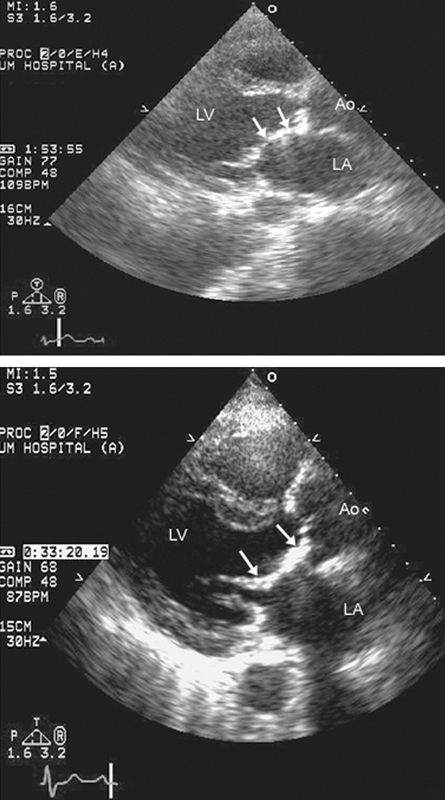

فحوصات تشخيصية لبعض امراض القلب والشرايين التاجية